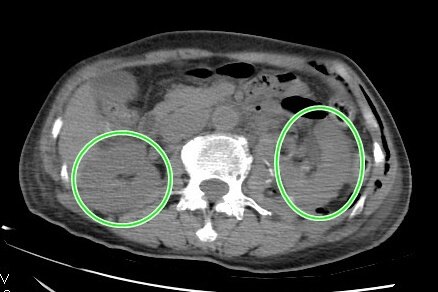

检查的影像显示,贡女士双侧肾肿均大于5公分,且左侧肾肿瘤位于肾门,靠近肾脏大血管、输尿管,有多支血管滋养供应。此类肿瘤手术常为“兵家禁地”,难度极大。手术时稍有偏差,就会损失大血管、输尿管,需切除整个肾脏。青大附院泌尿外科主任王科介绍,患者双侧都是巨大肿瘤,一旦一侧手术保肾失败,则给另一侧手术必然带来更大压力和挑战。如果双侧肾脏都丢失,就意味着患者将来面临终生透析,而肾脏移植价格昂贵,后续的治疗药物需要终身服用,对患者本人和她的家庭来说无疑是“灭顶之灾”。

三周后,患者再次入院,为第二次手术切除左侧肾肿瘤做准备。王科介绍,患者左侧肾脏肿瘤大于6厘米,且紧靠大血管和输尿管,利用腹腔镜技术保留肾脏、切除肿瘤,对手术技巧和缝合技术要求极高,手术难度非常大。手术要求切除肿瘤的同时既保证肿瘤完整,又要保护大血管和输尿管不受损。这种手术需要医生具备丰富的临床经验,娴熟的手术技巧和过硬的心里素质。王科在完成充分的术前准备之后,再次为患者实施腹腔镜下肾部分切除术(左侧)。手术时间历时90分钟,肾脏缺血时间20分钟。完整切除肾脏肿瘤后,成功保留左肾。患者术后恢复良好。术后复查CT,患者两侧肾脏形态良好,肾功能良好。患者及家属非常满意。